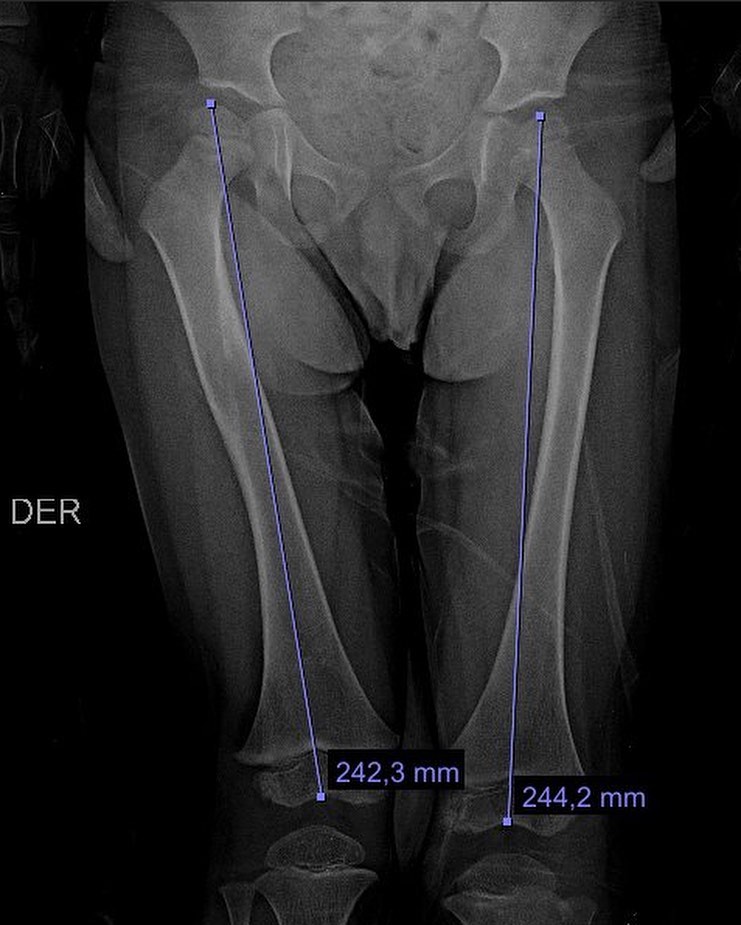

El año pasado mi pacientito Dylan se fracturó el fémur, realizamos tratamiento conservador y ahora está al 💯 Vino a consulta y recibí este delicioso regalo, ¡muchas gracias Dylan!